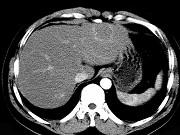

男54岁,B超体检示肝左叶强回声团块影,CT表现如图,最可能的诊断是()A.肝癌B.肝腺瘤C.肝母细胞瘤D.肝血管瘤E.肝脓肿

问题 男54岁,B超体检示肝左叶强回声团块影,CT表现如图,最可能的诊断是()

选项 A.肝癌 B.肝腺瘤 C.肝母细胞瘤 D.肝血管瘤 E.肝脓肿

答案 D